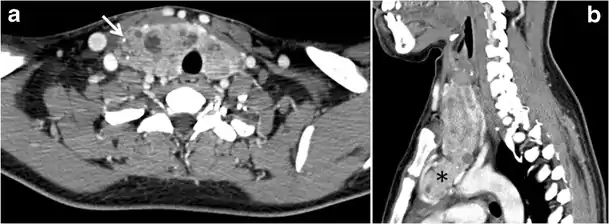

Fig. 13. A 27-year-old female patient known to have goiter. a, b Axial and sagittal enhanced CT scan images of the neck demonstrate a heterogeneously enhancing, enlarged thyroid gland with scattered calcifications (white arrow), cystic changes, and substantial retro-sternal extension (black asterisks). No lymphadenopathy or substantial airway narrowing.[1]

Fig. 14. A 19-year-old male patient known to have multi-nodular goiter and FNA, showing underlying Hashimoto's thyroiditis. a, b Sagittal and transverse greyscale and colour Doppler ultrasound of the neck demonstrate a hypoechoic enlarged right thyroid lobe with small hyperechoic regenerative nodules and marked hypervascularity (white arrows). c, d Enhanced axial CT scan images of the neck demonstrate a heterogeneously enhancing and enlarged thyroid gland, left more than right lobe, and the trachea is markedly narrowed.[1]